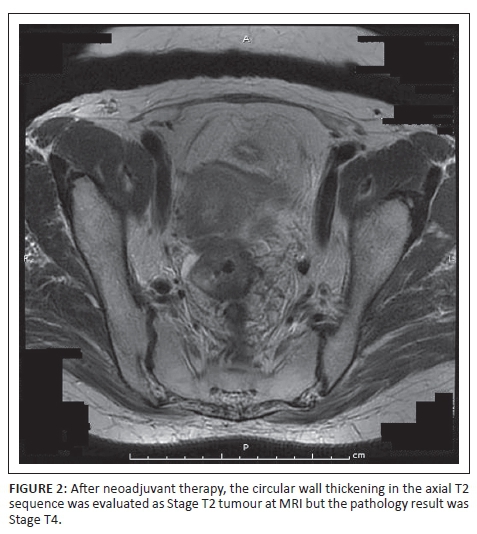

According to post-neoadjuvant therapy MRI scan staging, 3 patients were Stage 0, 5 patients were Stage 1, 13 patients were Stage 2a and 14 patients were Stage 3b. The postoperative pathology staging is summarised in Table 6. The results show, according to the TNM staging system, that in a total of 35 patients, 13 cases (37.14%) were overstaged (Figure 1a and b), 3 cases (8.57%) were downstaged (Figure 2) and 19 cases (54.28%) were correctly staged (Figure 3). Reasons for overstaging include fibrosis, desmoplastic reaction and lymphoplasmocytic infiltration. A reason for downstaging may be that MRI cannot differentiate tumour tissue. The accuracy of MRI in the overall staging according to the TNM staging system was 28%.